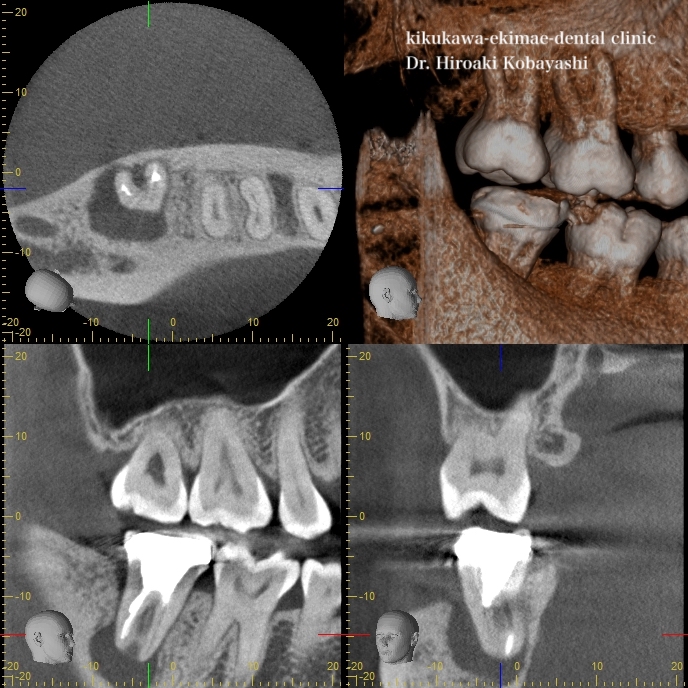

下の奥歯の根の治療というのは唾液が入りやすく、保険の限られた処置では感染が起こっていることがほとんどです。痛みが出ていないだけで、骨の吸収は刻一刻と進んでいます。根の先の黒い像が骨の吸収です。歯が骨に囲まれていなければ、歯は揺れて抜けます。この方も、もう後少し黒い箇所が広がれば歯が抜けることになります。

上の写真と比べると骨が再生し、根のがしっかりと固定されたのがお分かりかと思います。例え、歯の神経が無くなったとしてもセルフケアや力のセルフコントロールがなされば長期に渡って歯を残すことができます。それは抜いてインプラントをするよりも予知性のある治療になります。